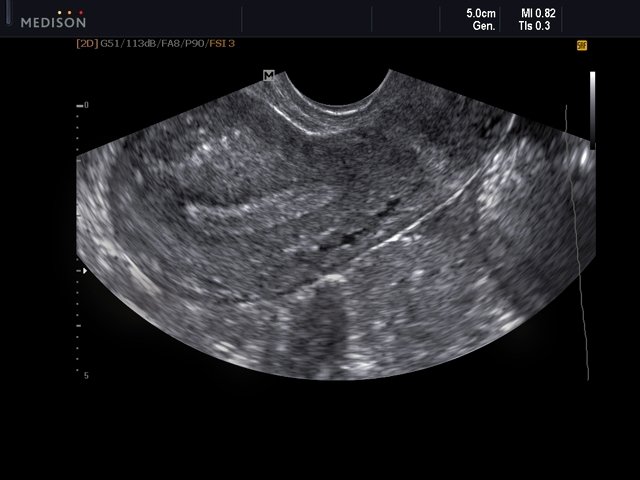

[RU] Ultrasound image №559: Endometrium (transvaginal scan) in B-mode.

Echogramm was received by ultrasound scanner SonoAce-R7 (out of production).